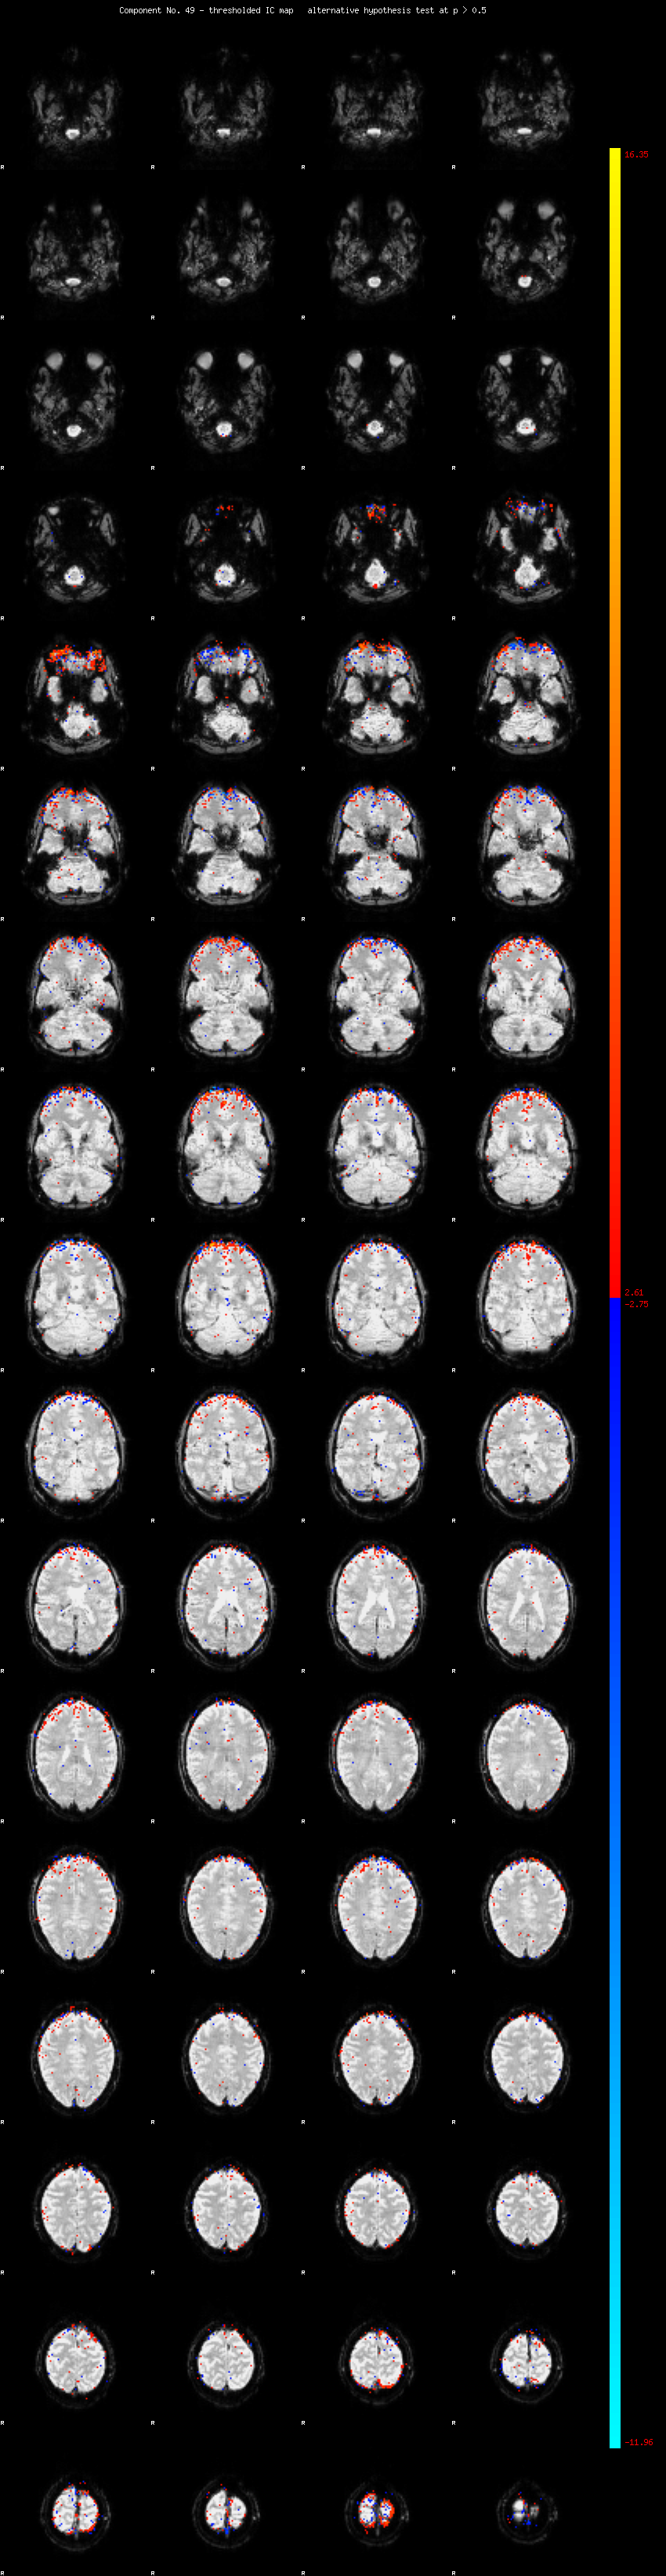

MELODIC Component 49

0.97 % of explained variance;     0.64 % of total variance

MMfit